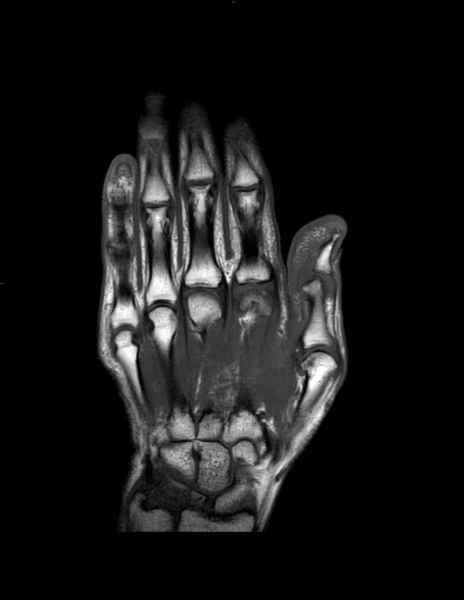

Técnica: Se realizó resonancia magnética de la mano izquierda en resonador de 1.5 teslas, con secuencias T1, T2, densidad protónica con y sin saturación de la grasa.

Hay aumento la cantidad de líquido que rodea los tendones extensores del segundo compartimento a nivel de la muñeca.

El resto los tendones regionales son de trayecto e intensidad de señal normal.

Las estructuras óseas son de morfología normal, se identifican quistes subcondrales en epífisis distal del primer metacarpiano así como osteofitos, también son evidentes pequeños osteofitos en ambas superficies de la articulación trapeciometacarpiana.

Tenosinovitis del segundo compartimento extensor.

Datos de artrosis trapeciometacarpiana y metacarpofalángica del primer dedo.